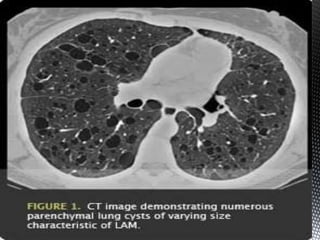

*CT scan and high-resolution CT scan findings include

the following:

 Diffuse thin-walled cysts - The defining appearance in LAM

Figure 1. Chest CT scan of a patient with LAM (A)

showing numerous thin-walled cysts distributed

throughout the lungs. (B) The lung parenchyma is

almost completely replaced by very small